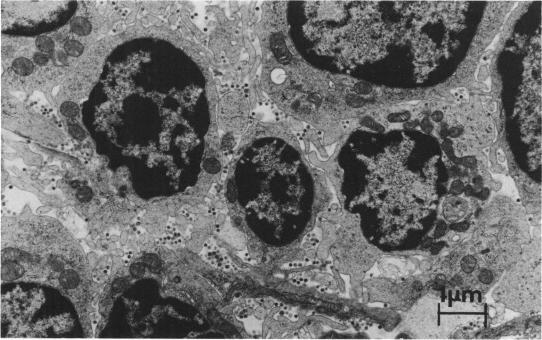

The efficacy of N-acetyl-nor-muramyl-L-alanyl-D-isoglutamine (nor-MDP) in controlling viral oncogenesis in mice was investigated. The tumors studied were blood cell malignancies induced by Friend leukemia virus in SJL/J mice, spontaneous mammary neoplasms in RIII/Imr and C3H/OuJ mice, and spontaneous lymphocytic leukemia in AKR/J mice. A transplantable tumor, Lewis lung carcinoma, in C57BL/6J mice was used as a nonvirally induced control model. The nor-MDP was dissolved in saline and made into an emulsion with an equal volume of squalene-Arlacel A and injected subcutaneously at 1- to 2-month intervals. Test and control mice were challenged with exogenous virus or tumor transplant 2 weeks after a second injection of nor-MDP. Administration was started at around 2 months of age in mice that develop spontaneous neoplasms. Electron microscopy studies were done on neoplastic tissues of selected test and control mice. This administration of nor-MDP prevented erythroleukemia in SJL/J mice caused by low doses of Friend leukemia virus (although erythroleukemia survivors were not protected from a late-developing lymphoma) and also delayed (possibly prevented) the development of a spontaneous mammary neoplasm in RIII/Imr mice. No antitumor effects were observed on the spontaneous neoplasms of C3H/OuJ and AKR/J mice or on the Lewis lung carcinoma implanted into C57BL/6J mice. Electron microscopic examinations of the various neoplastic tissues indicated that nor-MDP administration eliminated or reduced extracellular viruses. The results suggested that under the experimental conditions used nor-MDP appears to effect the viruses and not the malignant cells per se.

研究了N-乙酰-去甲-胞壁酰-L-丙氨酰-D-异谷氨酰胺(去甲-MDP)在控制小鼠病毒诱导肿瘤发生方面的功效。所研究的肿瘤包括SJL/J小鼠中由Friend白血病病毒诱导的血细胞恶性肿瘤、RIII/Imr和C3H/OuJ小鼠中的自发性乳腺肿瘤,以及AKR/J小鼠中的自发性淋巴细胞白血病。C57BL/6J小鼠中的可移植肿瘤——Lewis肺癌,用作非病毒诱导的对照模型。将去甲-MDP溶解于盐水中,与等体积的角鲨烯-阿拉塞尔A制成乳剂,每隔1至2个月皮下注射一次。在第二次注射去甲-MDP后2周,用外源病毒或肿瘤移植对试验组和对照组小鼠进行攻击。对于发生自发性肿瘤的小鼠,在约2月龄时开始给药。对选定的试验组和对照组小鼠的肿瘤组织进行了电子显微镜研究。这种去甲-MDP给药方案预防了低剂量Friend白血病病毒引起的SJL/J小鼠的红白血病(尽管红白血病幸存者未免受后期发生的淋巴瘤的影响),并且还延迟了(可能预防了)RIII/Imr小鼠自发性乳腺肿瘤的发生。未观察到对C3H/OuJ和AKR/J小鼠的自发性肿瘤或植入C57BL/6J小鼠的Lewis肺癌有抗肿瘤作用。对各种肿瘤组织的电子显微镜检查表明,去甲-MDP给药消除或减少了细胞外病毒。结果表明,在所使用的实验条件下,去甲-MDP似乎作用于病毒而非恶性细胞本身。